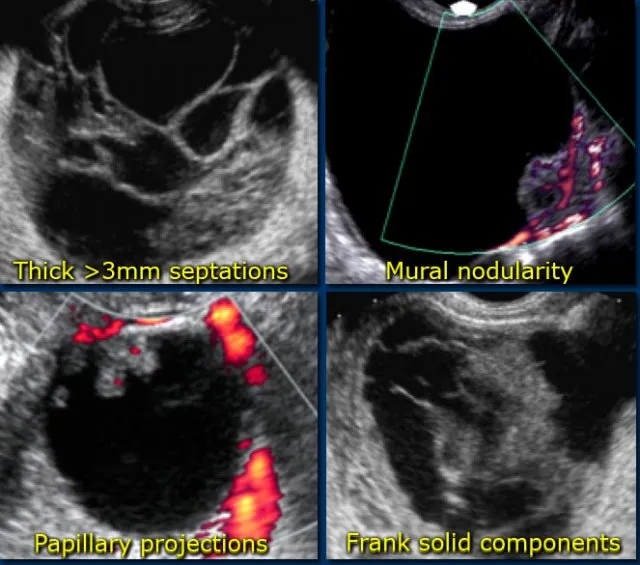

- Suspicious Features: Complex (solid & cystic), thick septations (>3 mm), papillary projections, solid nodules, increased vascularity on Doppler, ascites.